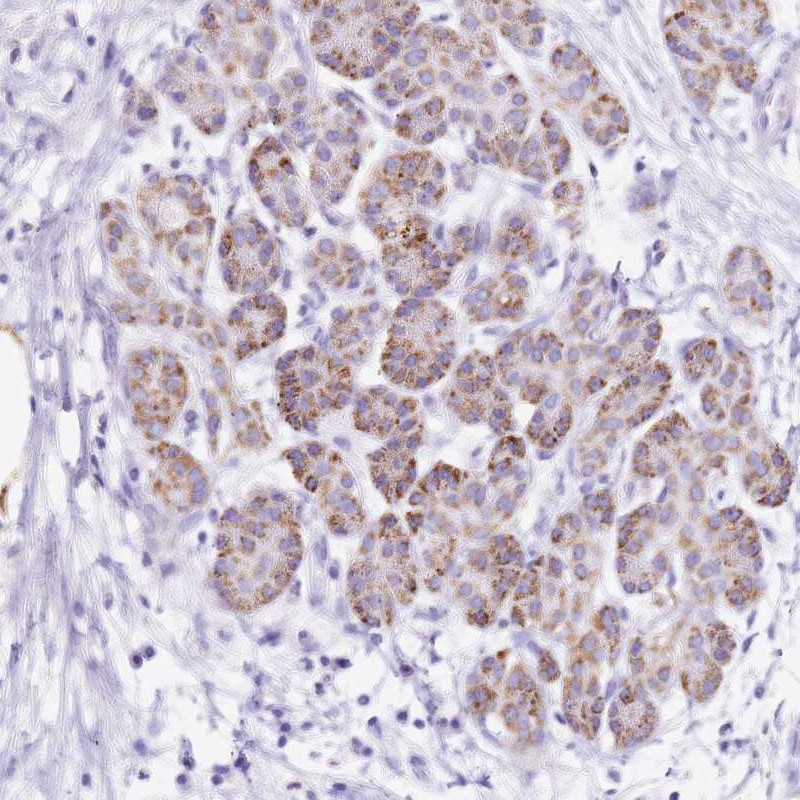

Immunohistochemical staining of human pancreas shows moderate cytoplasmic positivity in exocrine glandular cells.